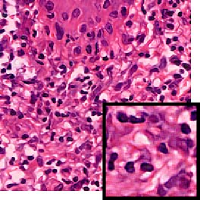

We demonstrate our WSI creation workflow on Leishmaniasis cases, as shown in Figures 1 and 4. An expert pathologist reviewed the cases and annotated granulomas as well as LD bodies on the stitched images and our generated images in Figure 4. To show generalizability of our approach, we also show results on core biopsies of breast, duodenum, stomach, liver, and lymph nodes (Figure 5).

| Breast | Duodenum | stomach | liver | lymph node | |||||